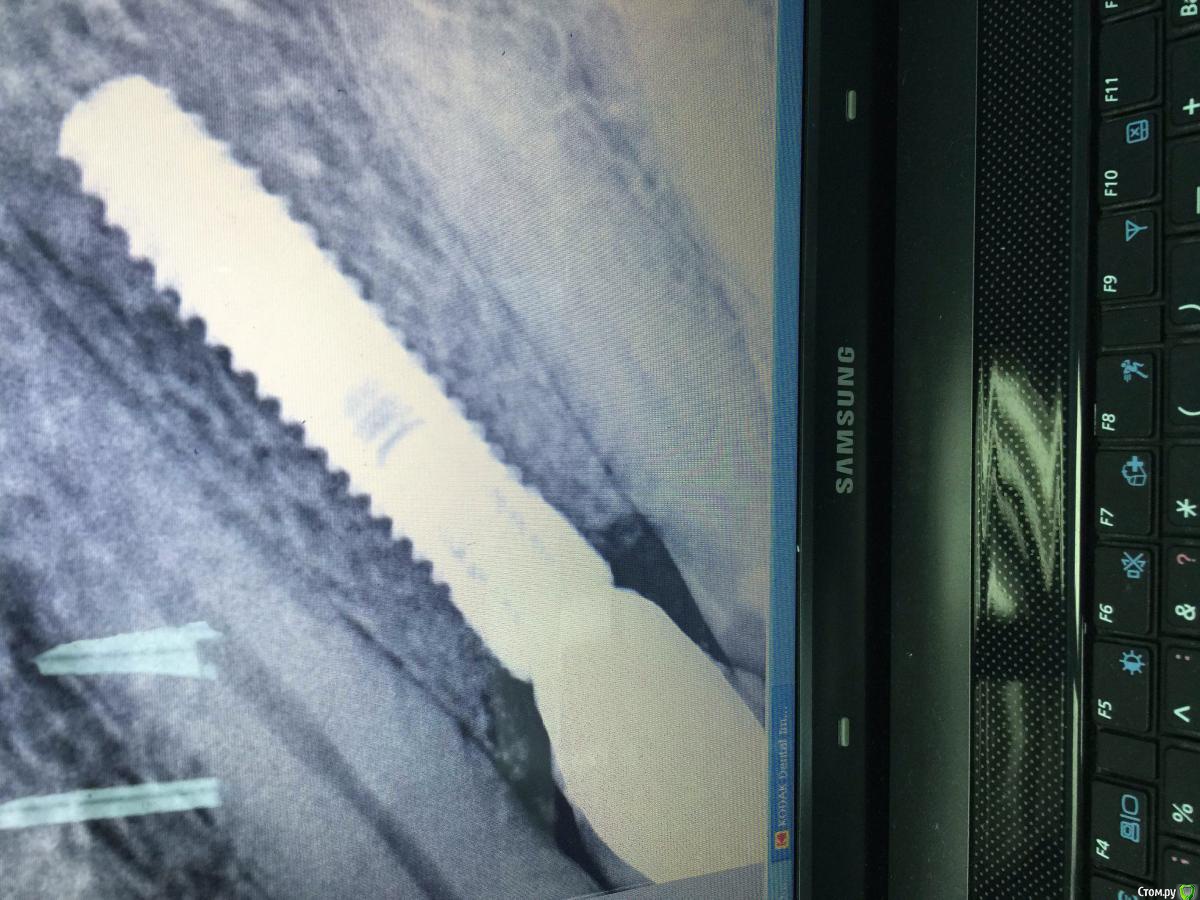

Вандышев Дмитрий Опубликовано 25 августа, 2015 Поделиться Опубликовано 25 августа, 2015 Подскажите .Десневой сосочек между 2.4и2.5 постоянно кровоточит при легком прикосновении.Имплант устанавливал 2.4 одномоментно с удалением и постановкой временной коронки.С временной коронкой кровоточивость была чуть меньше,после постановки постоянной коронки прошло 4-5месяцев и кровоточит практически всегда при прикосновении.Контактные пункты между 2.3и2.4и2.5 плотные.Зонд между 2.4и2.5 проваливается на 5-6мм,сосочек начинает уходить.Сосочек между 2.3и2.4 не кровоточит Ссылка на комментарий

hemchik Опубликовано 25 августа, 2015 Поделиться Опубликовано 25 августа, 2015 (изменено) может травмирует во время чистки зубов. там на 25 мезиально пломба? цемента вроде не видно Изменено 25 августа, 2015 пользователем hemchik Ссылка на комментарий

Вандышев Дмитрий Опубликовано 25 августа, 2015 Автор Поделиться Опубликовано 25 августа, 2015 (изменено) Какая фиксация постоянной коронки?цементная но на временной свинтовой фиксацией кровоточила меньше Изменено 25 августа, 2015 пользователем Вандышев Дмитрий Ссылка на комментарий